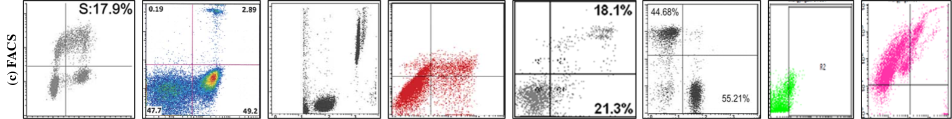

We classify the images from the previous collection step into four categories — (1) Microscopy (2) Blots/Gels (3) Flow-cytometry or Fluoroscence-activated cell sorting (FACS) and (4) Macroscopy. This taxonomy is made considering both the semantics and visual similarity of different image classes. Semantically, microscopy includes images from experiments that are captured using a microscope. They include images of tissues and cells. Variations in microscopy images can result from factors pertaining to origin (e.g. human, animal, organ) or fluorescent chemical staining of cells and tissues. This produces images of diverse colors and structures. Western, northern and southern blots and gels are used for analysis of proteins, RNA and DNA respectively. The images look similar and the specific protein or blot types are visually indistinguishable. FACS images look similar to synthetic scatter plots. However, the pattern is generated by a physical experiment which represents the scattering of cells or particles. Finally, Macroscopy includes experimental images that are visible to the naked eye and do not fall into any of the first three categories. Macroscopy is the most diverse image class with images including rat specimens, tissues, ultrasound, leaves, etc. Table 1 shows the composition of BioFors by image class. Figure 2 shows inter and intra-class diversity of each class. The image categorization discussed here is easily learnable by popular image classification models as shown in Table 2.